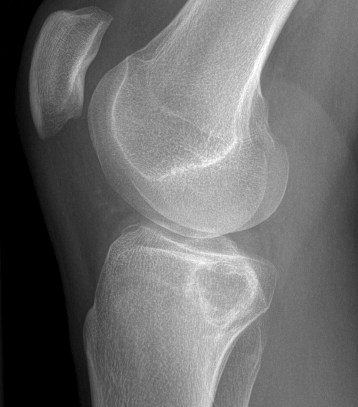

X-ray

Well defined eccentrically located epiphyseal lesion

- thin sclerotic reactive rim

- may have calcification

CT

Evaluate articular surface integrity / compromise

Identify chondroid matrix